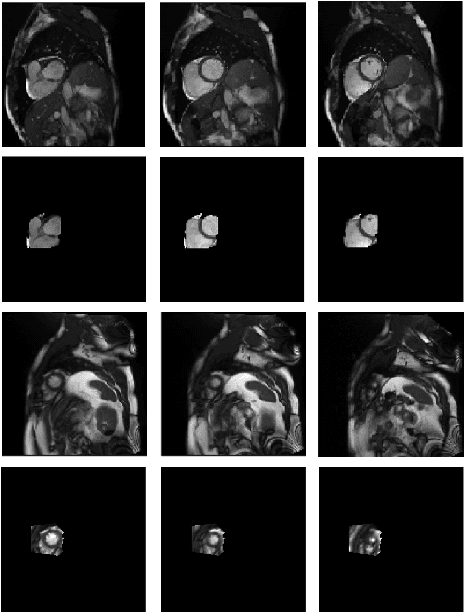

Abstract:Cardiovascular magnetic resonance (CMR) imaging has become a modality with superior power for the diagnosis and prognosis of cardiovascular diseases. One of the essential basic quality controls of CMR images is to investigate the complete cardiac coverage, which is necessary for the volumetric and functional assessment. This study examines the full cardiac coverage using a 3D convolutional model and then reduces the number of false predictions using an innovative salient region detection model. Salient regions are extracted from the short-axis cine CMR stacks using a three-step proposed algorithm. Combining the 3D CNN baseline model with the proposed salient region detection model provides a cascade detector that can reduce the number of false negatives of the baseline model. The results obtained on the images of over 6,200 participants of the UK Biobank population cohort study show the superiority of the proposed model over the previous state-of-the-art studies. The dataset is the largest regarding the number of participants to control the cardiac coverage. The accuracy of the baseline model in identifying the presence/absence of basal/apical slices is 96.25\% and 94.51\%, respectively, which increases to 96.88\% and 95.72\% after improving using the proposed salient region detection model. Using the salient region detection model by forcing the baseline model to focus on the most informative areas of the images can help the model correct misclassified samples' predictions. The proposed fully automated model's performance indicates that this model can be used in image quality control in population cohort datasets and also real-time post-imaging quality assessments.